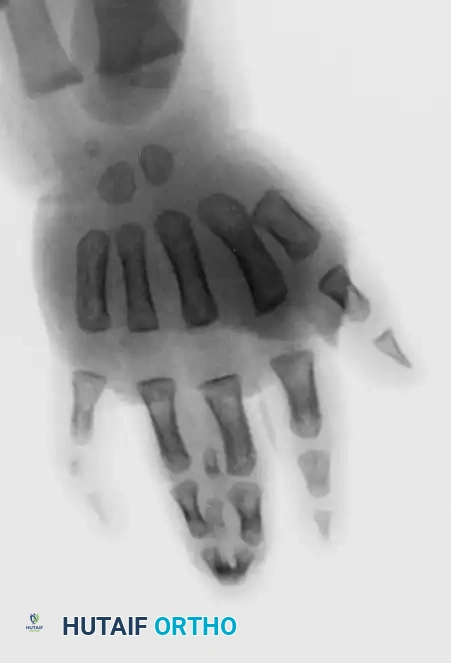

Fig. 76-33 Simple syndactyly. Fingers are bridged only by skin and other soft tissues. A, Palmar view. B, Dorsal view. C, Radiograph. Note the angular deformity of the ring finger.